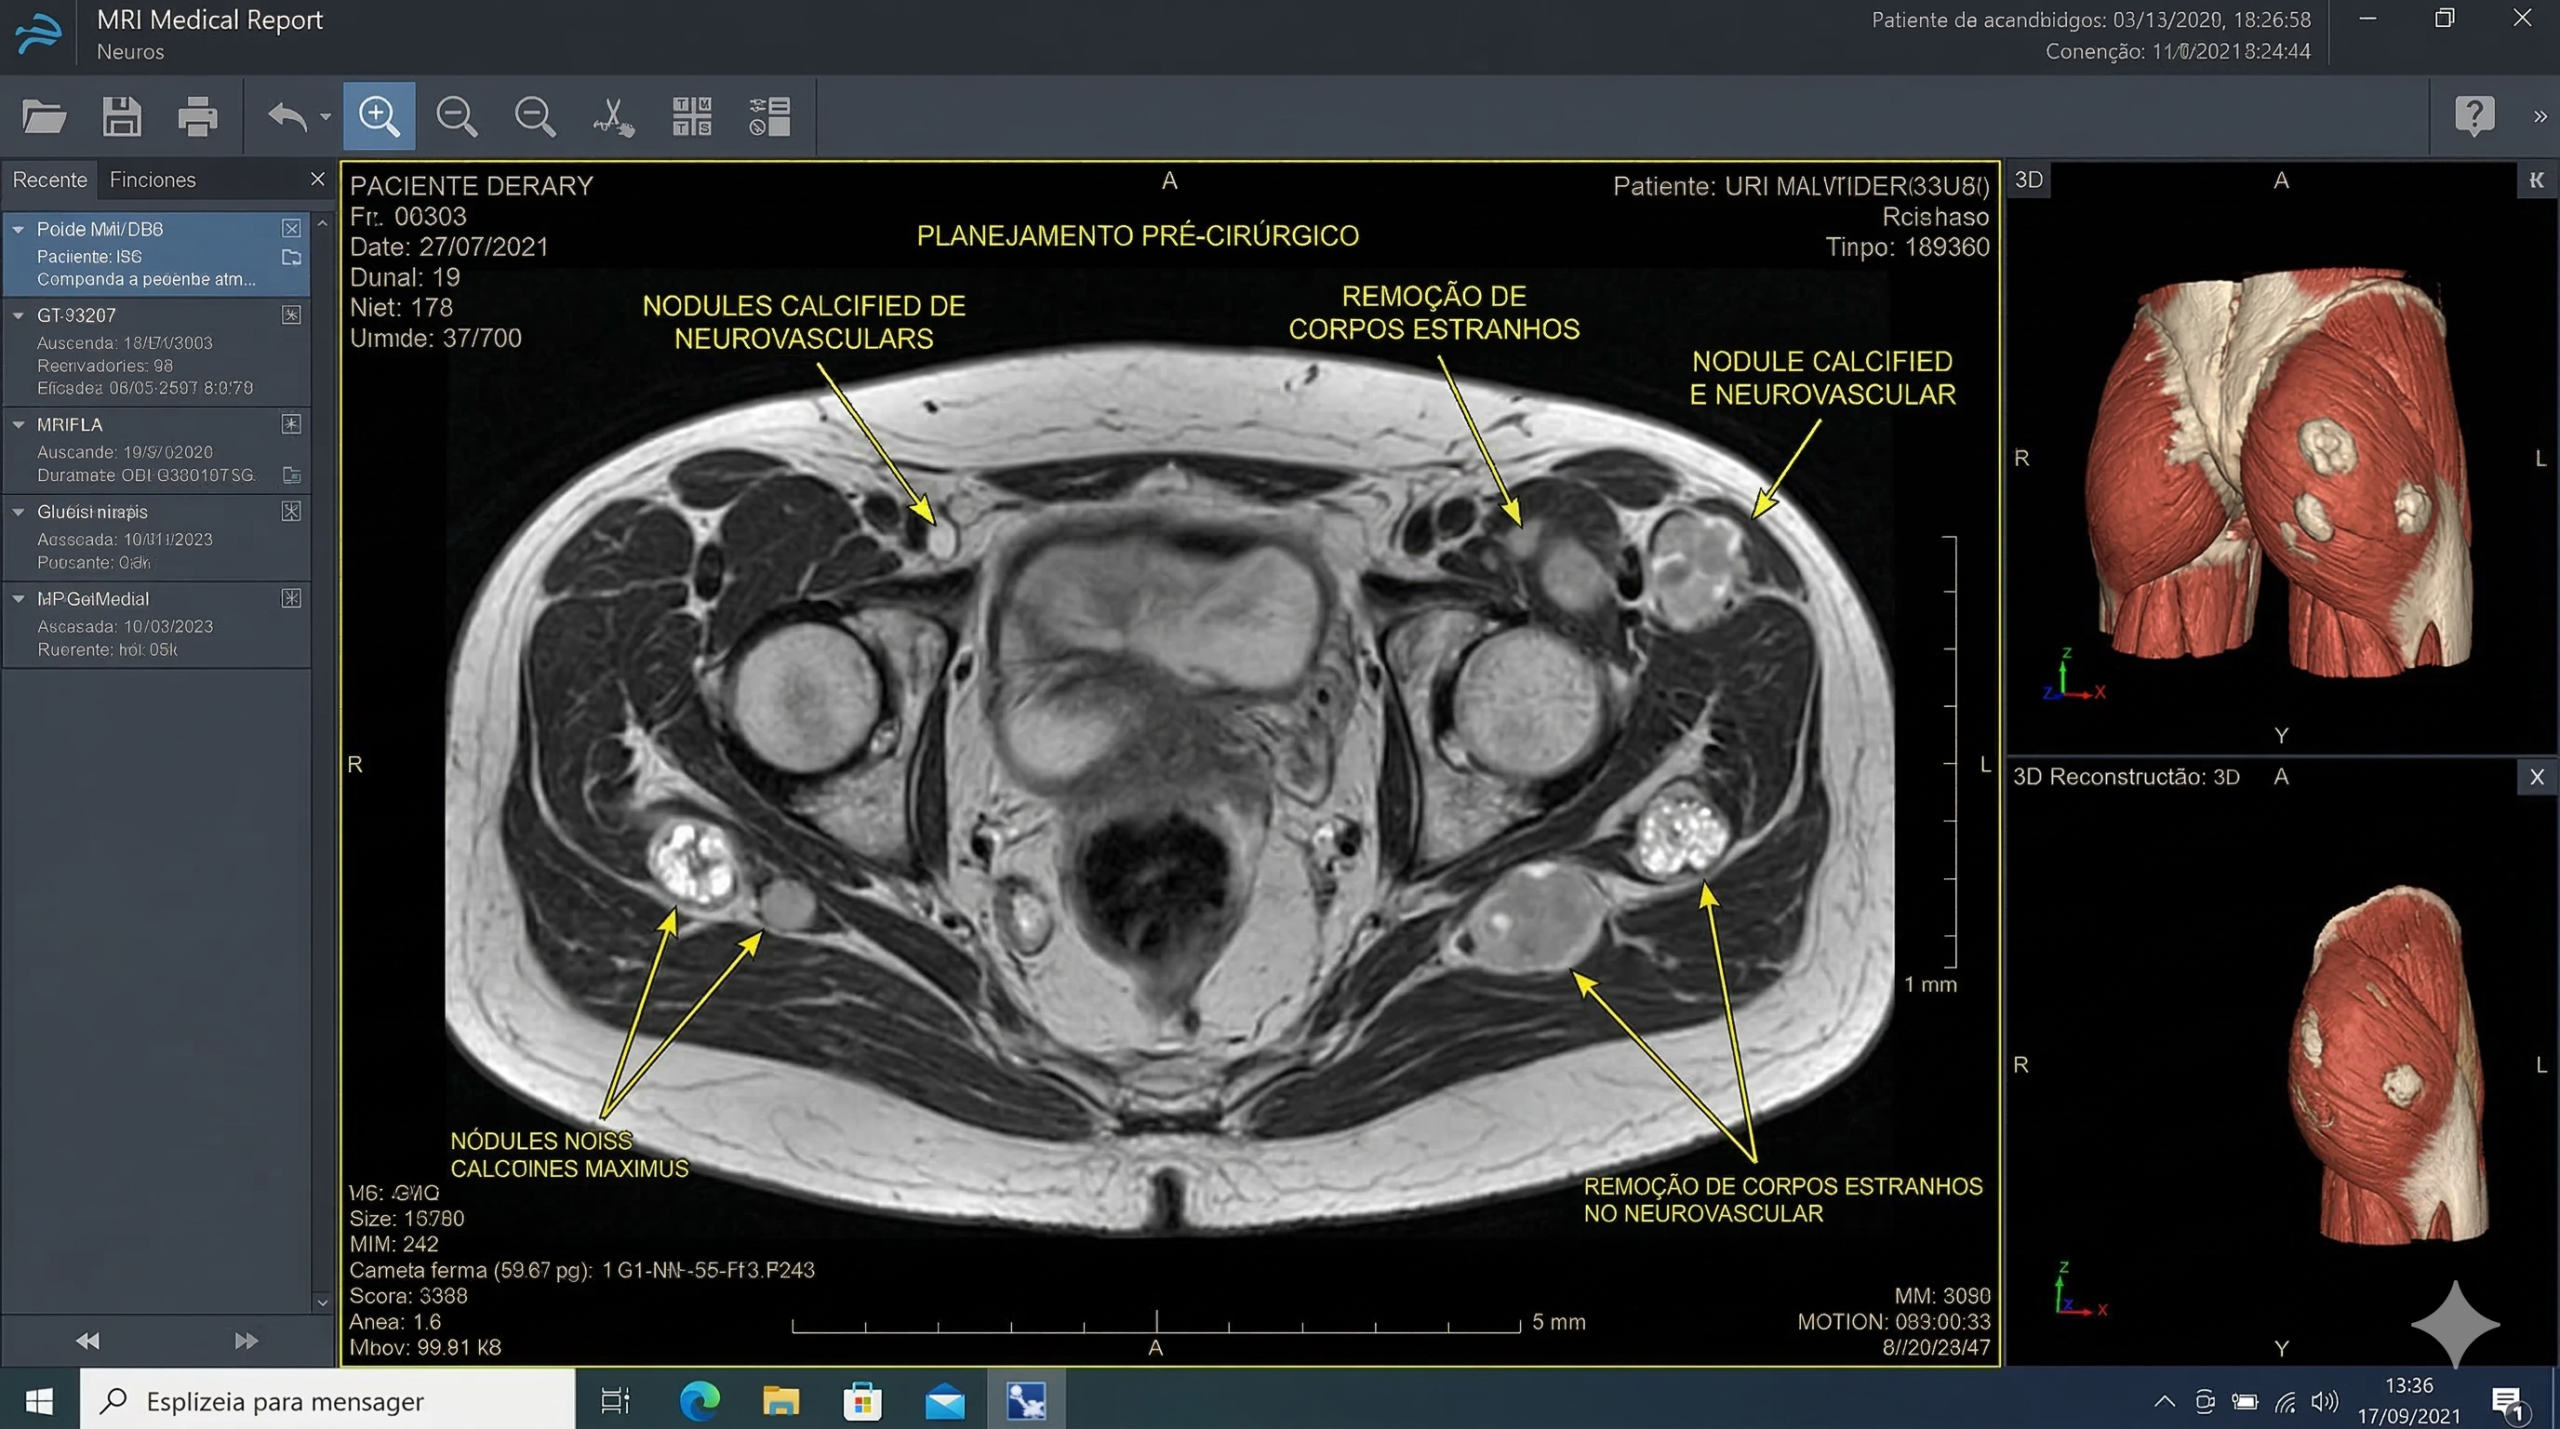

A dúvida não precisa consumir a sua saúde mental. Se você apresenta qualquer um dos sinais acima, não tente furar o local nem faça drenagens ou preenchimentos em cima do produto antigo. O diagnóstico não é feito “no olho”. O cirurgião plástico solicitará uma Ultrassonografia Dermatológica (de alta frequência) ou uma Ressonância Magnética com Contraste.

Na tela do radiologista, a diferença é brutal e indiscutível: o Ácido Hialurônico aparece como poças líquidas uniformes e anecoicas (pretas na imagem). O PMMA e o Silicone Industrial aparecem na imagem radiológica provocando um forte artefato conhecido como “tempestade de neve” — uma bagunça de manchas brancas e granuladas espalhadas entre os músculos, comprovando a presença do polímero invasivo. Com esse laudo em mãos, inicia-se o planejamento seguro para a remoção cirúrgica com o Dr. Carlos Neves.